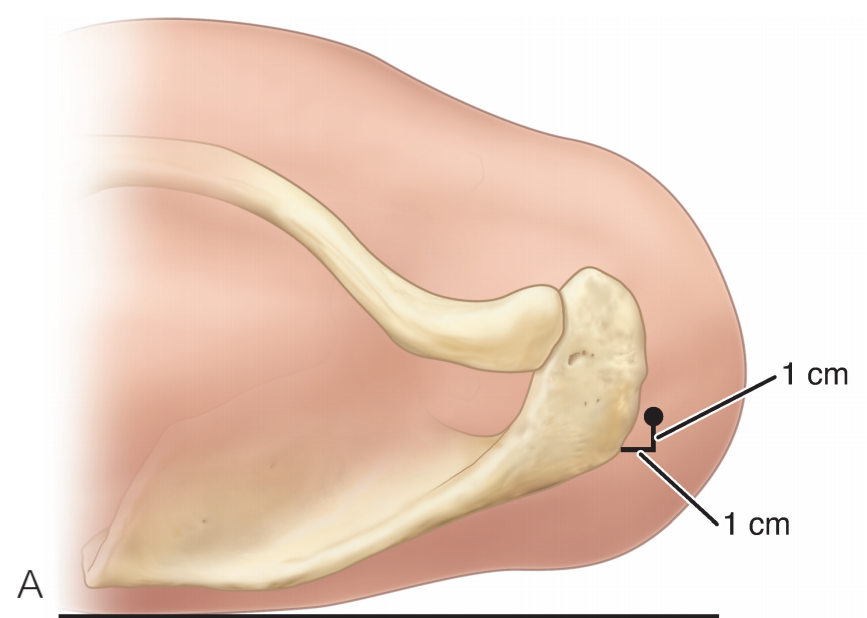

B. 应首先用腰椎穿刺针确定辅助入路的恰当位置和方向。然后在皮肤上做一个小切 A B 口,钻头导向器置入关节。